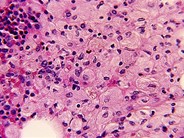

A 7-year-old girl presented with coarse facial features, cardiomegaly, intellectual disability, seizures, and macular cherry red spot. A mucopolysaccharidosis (MPS) disorder was suspected. Hepatosplenomegaly was absent. A comprehensive metabolic panel revealed normal kidney, liver, and thyroid function (thyrotropin: 1.75 μU/mL; T4: 9.5 μg/dL; blood urea nitrogen: 17 mg/dL; creatinine: 0.38 mg/dL), and the level of glycosaminoglycans in urine was normal (urine MPS: 4.2 mg/mmol creatinine), which excludes most of the common MPS disorders. Hematologic parameters showed hemoglobin:11.8 g/dL; white blood cells: 4.48 × 109/L; platelets: 234 × 109/L. There was mild neutropenia (absolute neutrophil count: 1.75 × 109/L). However, the blood film showed prominent cytoplasmic vacuoles in peripheral blood lymphocytes (panels A-F; 100× objective, total magnification ×1000; Wright's stain) suggestive of a storage disorder. Whole exome sequencing revealed a diagnosis of galactosialidosis due to homozygous mutations in the CTSA gene (c.556C>A: p. P186T).

Lysosomal storage disorders (LSDs) are a group of rare inherited diseases, and patients frequently encounter delay in diagnosis. Cytoplasmic vacuoles in neutrophils and monocytes are seen in a variety of conditions due to the phagocytic function of these cells (panel G; 100× objective, total magnification ×1000; Wright's stain). Vacuoles in mature lymphocytes should raise suspicion of an LSD.